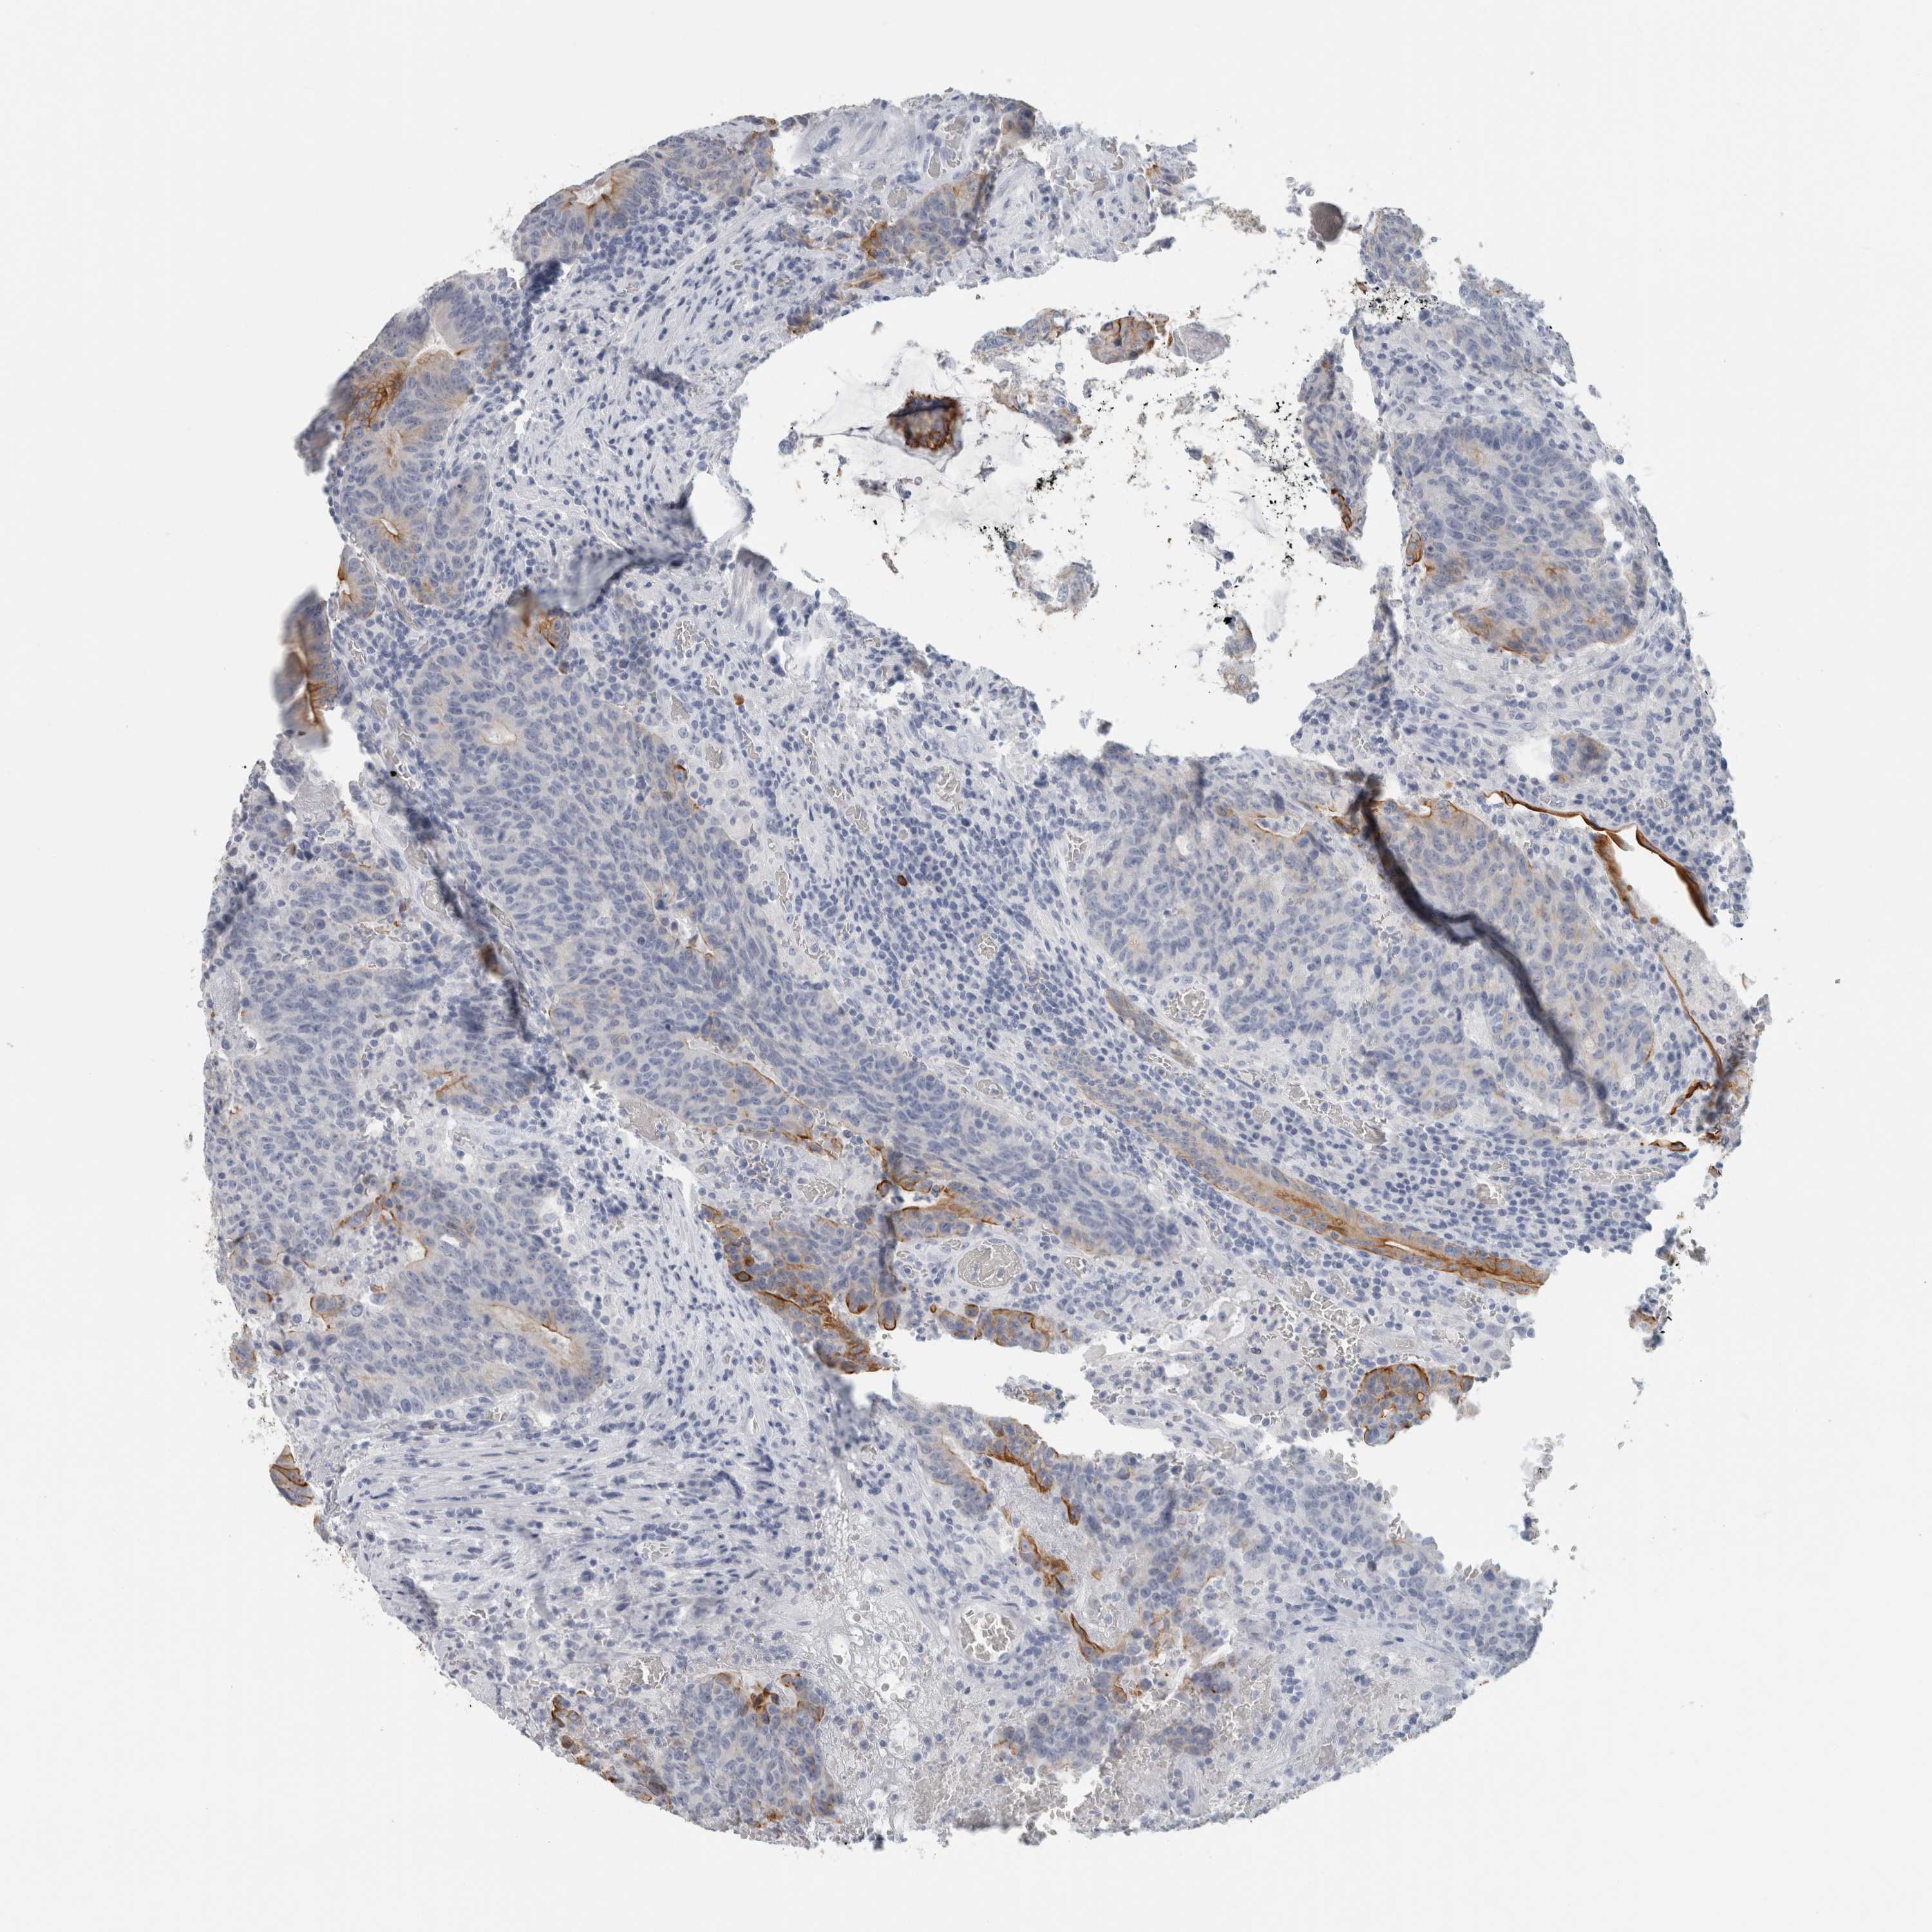

CANCER COLORECTAL CANCER Show tissue menu

Colorectal cancer

Human cancer

Colon adenocarcinoma